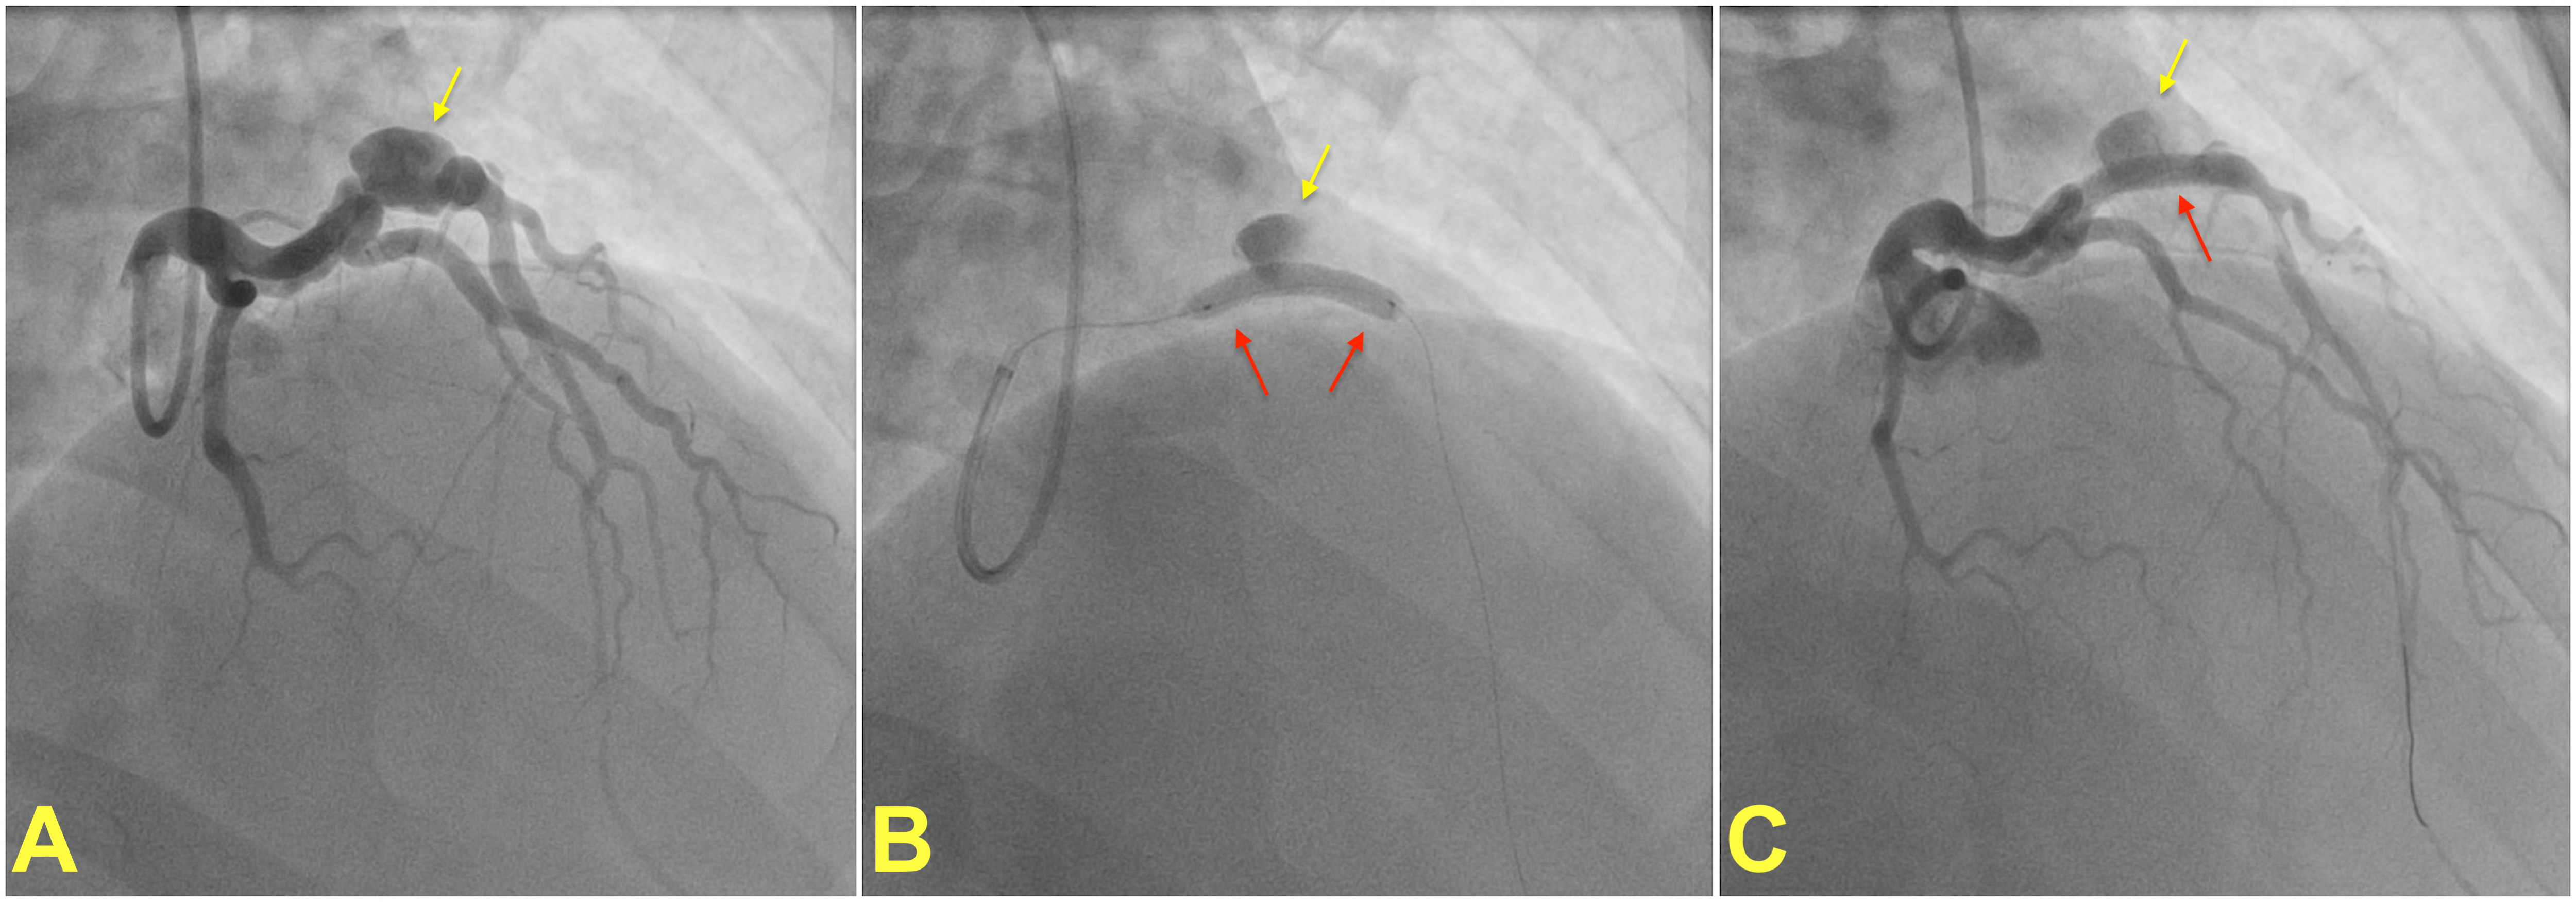

Fig. 2.

Fig. 2.

Percutaneous treatment of a coronary artery aneurysm. (A) shows coronary angiogram of a patient with a saccular coronary aneurysm (yellow arrow) on the left anterior descending artery. A covered stent (red arrow) is placed and deployed to isolate the aneurysm from the coronary circulation (B). (C) shows the final result after post-dilatation of the covered stent with a noncompliant balloon. Note that the contrast within the aneurysm is residual and does not indicate stent failure. Images courtesy of Dr. Muslum Sahin.